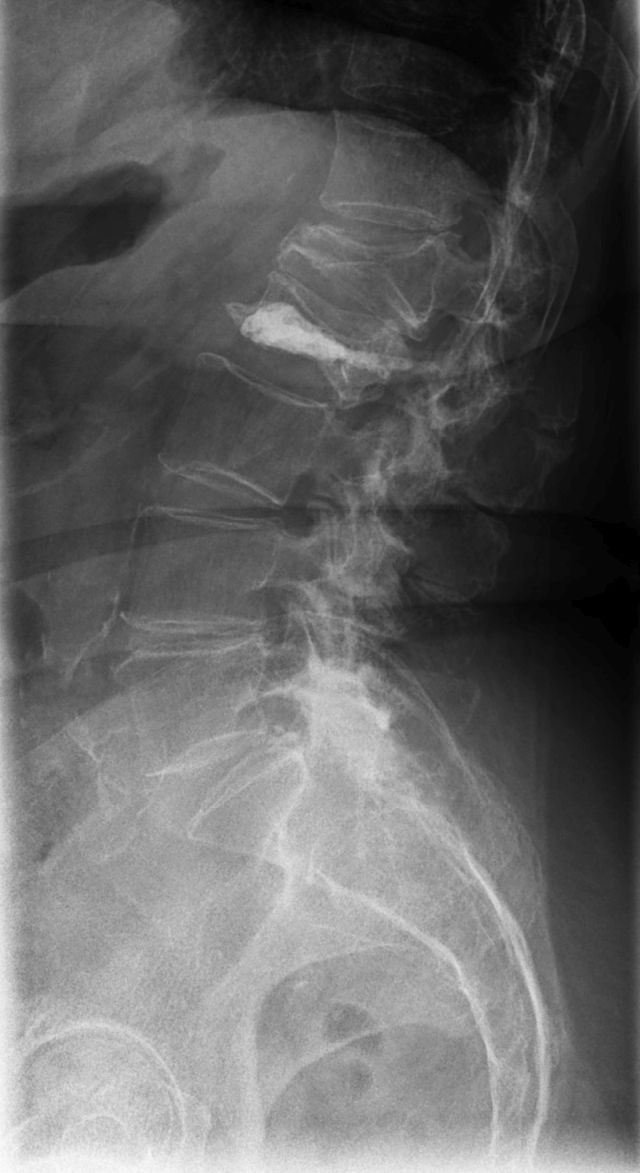

Osteoporose bedeutet wörtlich "poröser Knochen". Es handelt sich um eine systemische Skeletterkrankung, die durch eine niedrige Knochenmasse und eine mikroarchitektonische Verschlechterung des Knochengewebes charakterisiert ist. Die Knochen werden brüchiger und anfälliger für Brüche, die schon bei geringfügigen äußeren Anlässen wie Stürzen oder Stößen oder sogar unter Alltagsbelastungen auftreten können. Die häufigsten Stellen für Osteoporose-bedingte Brüche sind die Wirbelkörper in der Lendenwirbelsäule, der Oberschenkelhals und die Speiche im Handgelenk (Radiusfraktur). Sind bereits Brüche als Folge der Osteoporose aufgetreten, so liegt eine manifeste Osteoporose vor. Die Symptome der Osteoporose sind durch Knochenbrüche und ihre Folgen geprägt, die zu einer deutlichen Einschränkung der Lebensqualität führen, insbesondere bei hüftnahen Frakturen. Es gibt keine eindeutigen Beschwerden der Osteoporose, die Brüchen vorausgehen.

5. ggf. bildgebende Diagnostik bei Hinweisen auf osteoporotische Wirbelkörperfrakturen